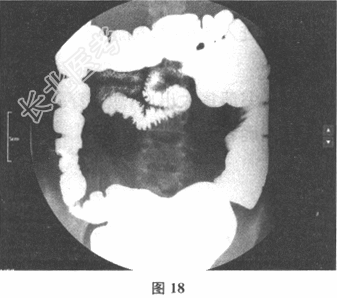

- 多项选择题2.[提示] 上消化道造影见图17,钡灌肠造影见图18。

该患者主要的诊断是( ) A、十二指肠空肠短路

D、十二指肠结肠短路

- 多项选择题3.[提示] 影像学表现明确诊断为十二指肠结肠短路。你认为合理的治疗策略是( )